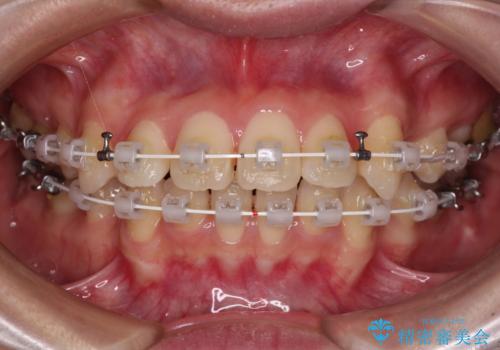

- 審美装置

- 2年4ヶ月

上下左右第一小臼歯4本を抜歯し、ワイヤー装置にてデコボコを解消しながら口元を引っ込めるよう矯正治療を行うこととしました。

抜歯スペースを閉じている過程で、左側の上下犬歯が引っかかってしまい、進捗が停滞しましたが、当初予定の2年~2年半の間で無事に治療を終えることができました。